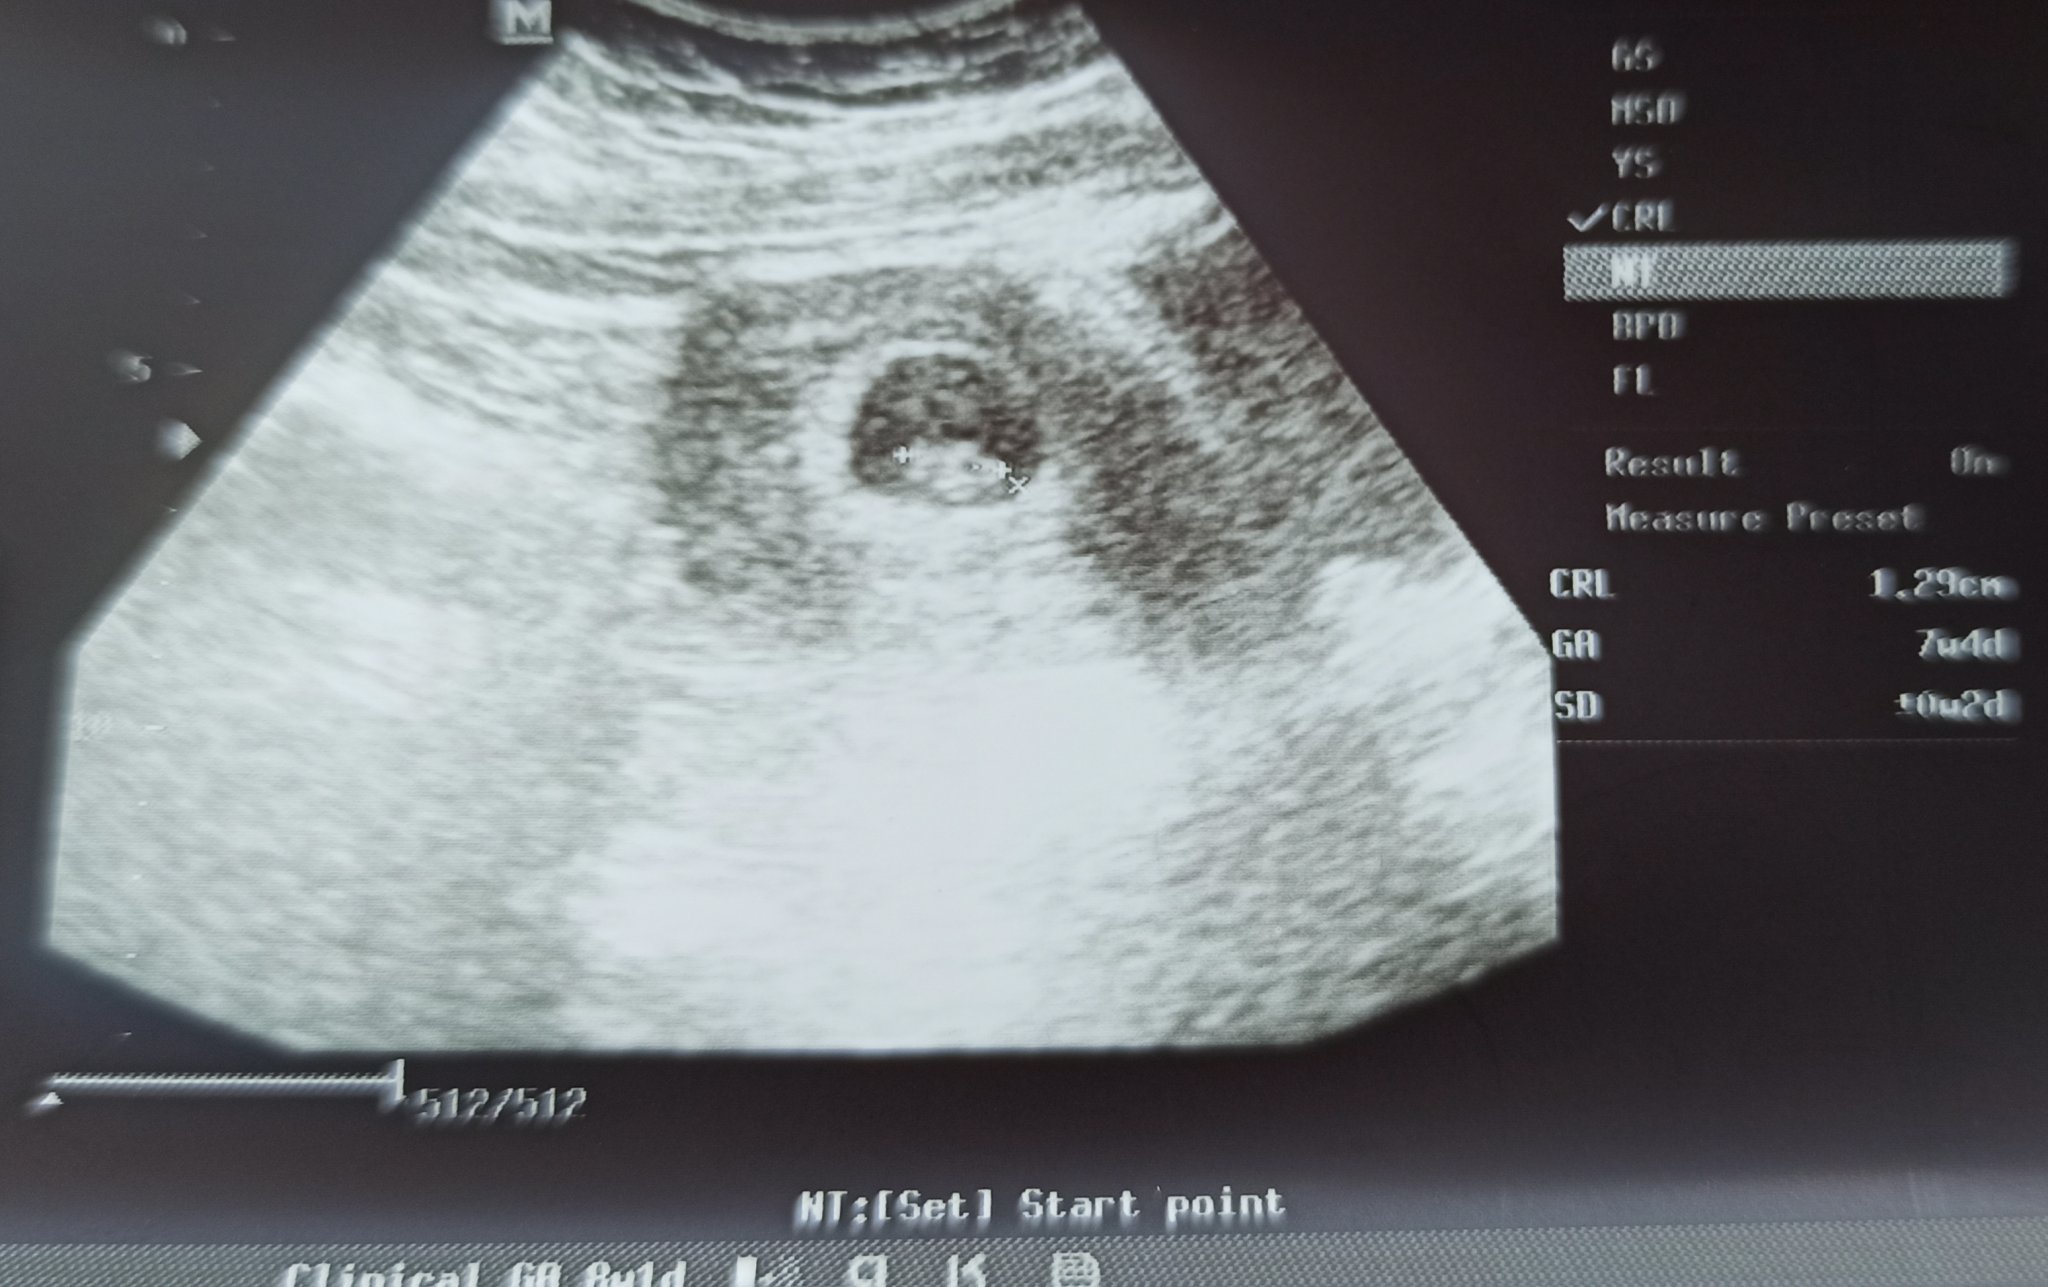

Днес най-после минах първия си преглед. Видя се сърдечна дейност. по календар съм 8 + 1, а според машината 7 + 4